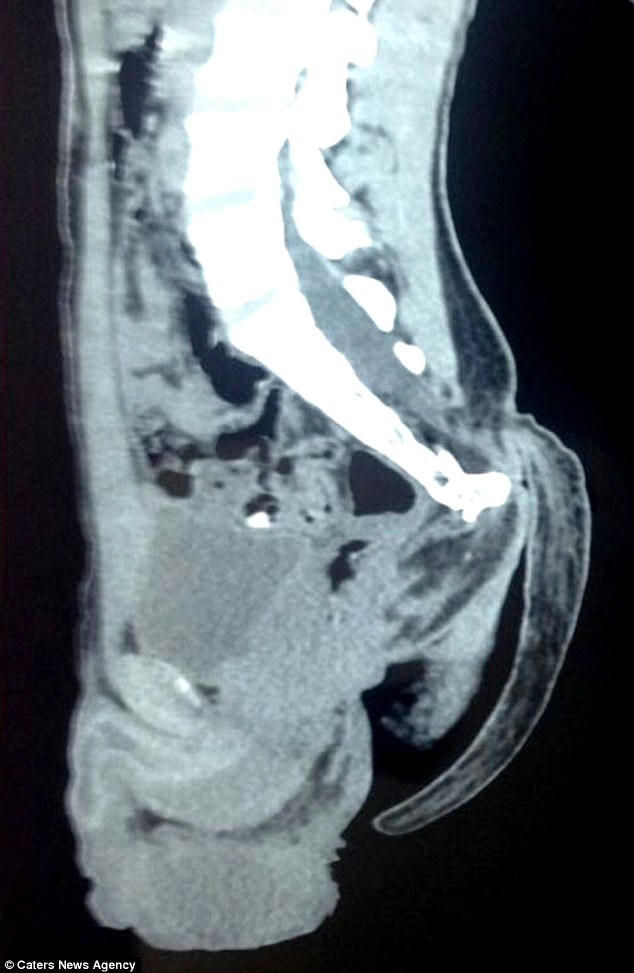

Theo Dailymail, các bác sĩ vừa hoàn thành ca phẫu thuật dài hơn 1 giờ cắt bỏ chiếc đuôi dài 17,78 cm trên người một nam thanh niên người Ấn Độ.

Nam thanh niên 18 tuổi, sống ở Nagpur, Ấn Độ đã nhập viện trong tình trạng có một cái đuôi phía cuối lưng ngày một lớn và gây đau đớn.

Sau khi kiểm tra các bác sĩ cho rằng cái đuôi là dấu tích hình thành trong quá trình phát triển trong bào thai.

Thông thường sau tuần thứ 6 của thai kỳ, bất cứ trẻ nào cũng hình thành một chiếc đuôi nhưng nó sẽ tự biến bất theo thời gian. Việc vẫn còn đuôi khi sinh ra là do sai sót trong quá trình hình thành cột sống trong bào thai.

Tuy nhiên trường hợp nam thanh niên này thật đặc biệt. Chiếc đuôi vẫn tồn tại và tiếp tục phát triển cho đến tận bây giờ.

Theo các bác sĩ chiếc đuôi không gây ra vấn đề sức khỏe nghiêm trọng nào cho bệnh nhân nhưng lâu dài sẽ gây ảnh hưởng tới cột sống và khả năng hoạt động của ruột cũng như gây đau đớn.

Ca phẫu thuật không quá khó khăn và nguy hiểm vì tại đuôi không có xương nhưng cần sự cẩn thận vì có phần của tủy sống.